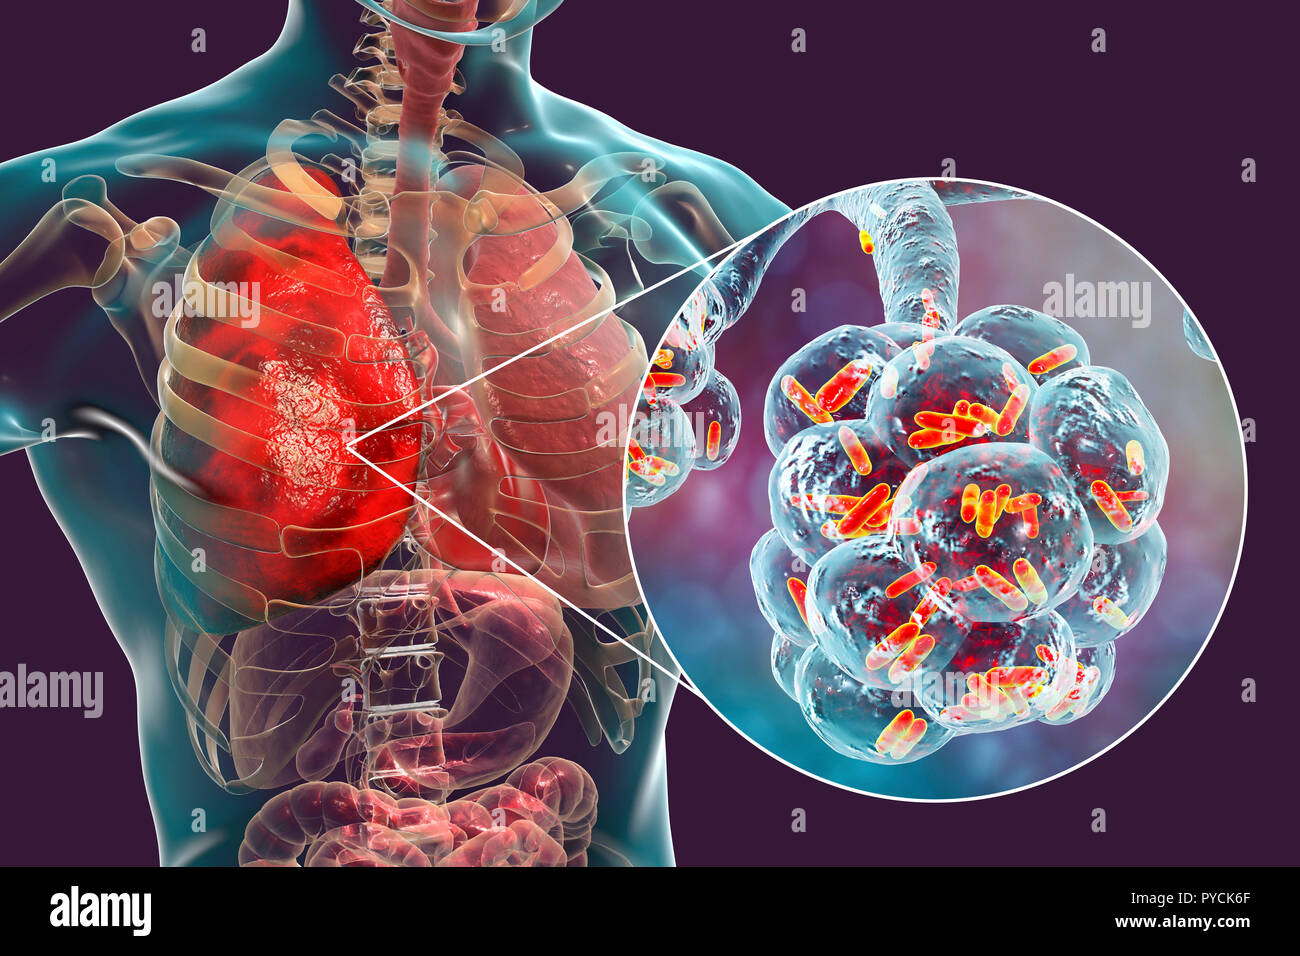

Prise en charge des infections des voies respiratoires basses de l'immunocompétent. Partie concernant les définitions, l'épidémiologie et les éléments du diagnostic Managing lower.

Infections respiratoires basses de l'enfant. Le diagnostic d'infection respiratoire chez l'enfant repose sur une triade symptomatique : fièvre, toux et difficultés respiratoires d'intensité.

De nombreux agents pathogènes peuvent provoquer des infections des voies respiratoires. Bon nombre de ces infections produisent des signes et des symptômes similaires, mais.

Selon l'Organisation mondiale de la santé, les infections des voies respiratoires telles que la tuberculose, la grippe et la pneumonie ont été responsables de plus de 4 millions de.